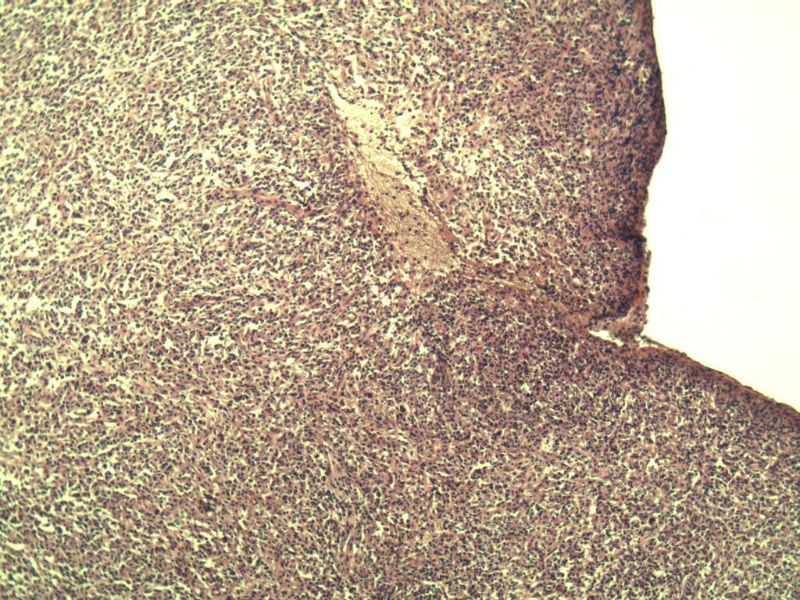

男,38岁,腹股沟 多枚淋巴结活检  直径 0.2-0.5 请各位老师看看 是什么 谢谢了!

"畏寒,发热咳嗽1年,加重伴腹部疼痛2月" 2月前患者感腹部疼痛不适伴大便呈稀大便,量不详,伴腰骶部疼痛,胸片:纵膈及右肺门多发性淋巴结肿大,进一步完善胸部CT:右肺及中叶病变,纵膈及肺门多发淋巴结肿大,结核性可能,脾脏增大,PPD(-),1个月来患者出现中上腹食欲不振,体重进行性消瘦,全身疲乏无力,3天前到医学院就诊,腹部B超:右肝囊肿,胆囊壁毛糙,脾大,胰周多个减弱回声,淋巴结不能除外,腹水,血常规示:WBC16.36x109 /L,N%14.25%,RBC2.63x1012/L ,HGB 66g/L 。右侧腋窝及腹股沟可扪及多枚淋巴结,压痛,无明显粘连。

腹股沟 多枚淋巴结活检图1

副皮质区增生,纤维化显著,细胞呈多形性,有一些多核巨细胞及一些异型细胞,病理性核分裂易见,胞浆红染,散在的小淋巴细胞,T细胞淋巴瘤不能除外,树突细胞肉瘤等鉴别。免疫标记。CD21、CD3、CD5、CD10、CD20、CD79a、PD1、CD68、CXCL13、KI-67、CD68、CD163等,据切片选择。不知对否。

淋巴结正常结构破坏,可见大的异型细胞,上皮样或梭形,恶性肿瘤,依据病史,首先考虑淋巴造血系统疾病,大中小细胞混杂,大细胞多,形态多样,可见多核瘤细胞,除以上考虑外需鉴别间变大、组织细胞肉瘤、指状突/树突细胞肿瘤、HL等,还需排除肉瘤或癌转移,尽管病人年轻,加上ALK、CK、S-100、CD1a。